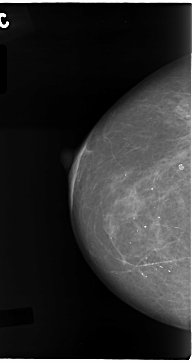

C_0111_1.RIGHT_CC

RIGHT_CC LINES 4712 PIXELS_PER_LINE 2488 BITS_PER_PIXEL 12 RESOLUTION 50 NON_OVERLAY